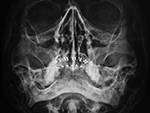

| 78 year-old woman with sinus headaches. Incidental presence of dentures (false teeth). Note air-fluid levels in both maxillary sinuses. |